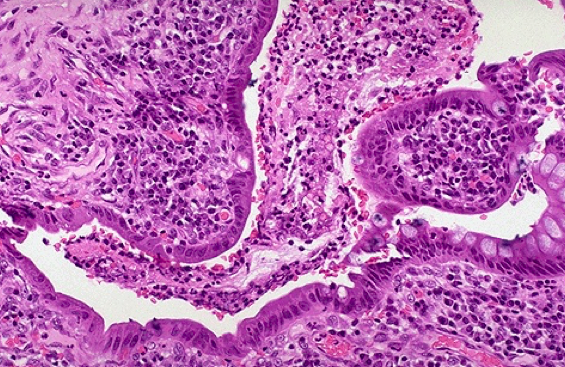

What is going on in these 2 images?

What do you see here?